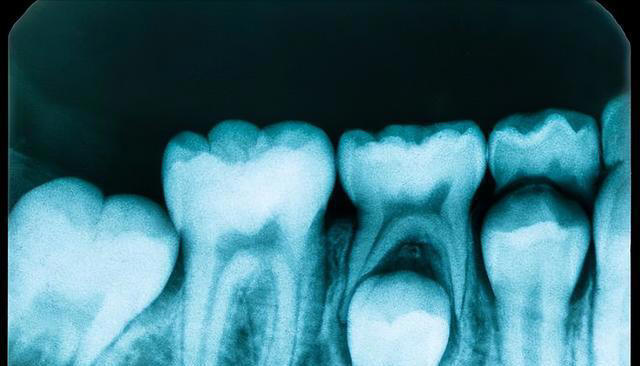

事实上,随着年龄的增长,我们的口腔也会发生一些变化。比如牙齿容易变脆,牙龈容易退缩,这些都需要我们在刷牙时更加小心,采取一些不同的护理方式。 首先,很多人认为早晚各刷一次牙就足够了,但实际上,早晚刷牙并不是最理想的方式。 特别是对于60岁以上的人群来说,早晚刷牙可能并不能彻底清洁口腔。 早上起床后,口腔内有大量的细菌和食物残渣,光是早晨刷牙可能不能彻底清除这些东西,而晚上刷牙时,很多人又容易忽视牙齿缝隙中的食物残渣。

随着时间的推移,这些细菌会积累,进而影响到牙齿和牙龈的健康。 医生建议,老年人可以考虑一天刷三次牙,特别是餐后及时刷牙,这样可以更有效地清除口腔中的细菌和残渣,减少口腔问题的发生。 另外,很多人习惯用硬毛牙刷刷牙,认为这样可以更彻底地清洁牙齿。 但是,过硬的牙刷毛容易对牙龈造成刺激,甚至可能导致牙龈出血和退缩,尤其对于老年人来说,牙龈退缩的风险更高。老年人的牙龈本身就较为脆弱,如果再使用硬毛牙刷,可能会加重退缩的情况。 医生建议,老年人最好选择软毛牙刷,这样既能有效清洁牙齿,又不容易伤害牙龈。